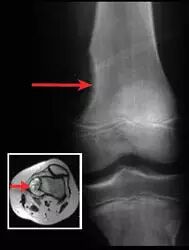

![]()

股骨(大腿骨)肿瘤。该X射线显示在大腿骨末端引起类似茶碟的侵蚀的肿瘤。插图是使用横截面磁共振图像(MRI)显示相同的肿瘤。